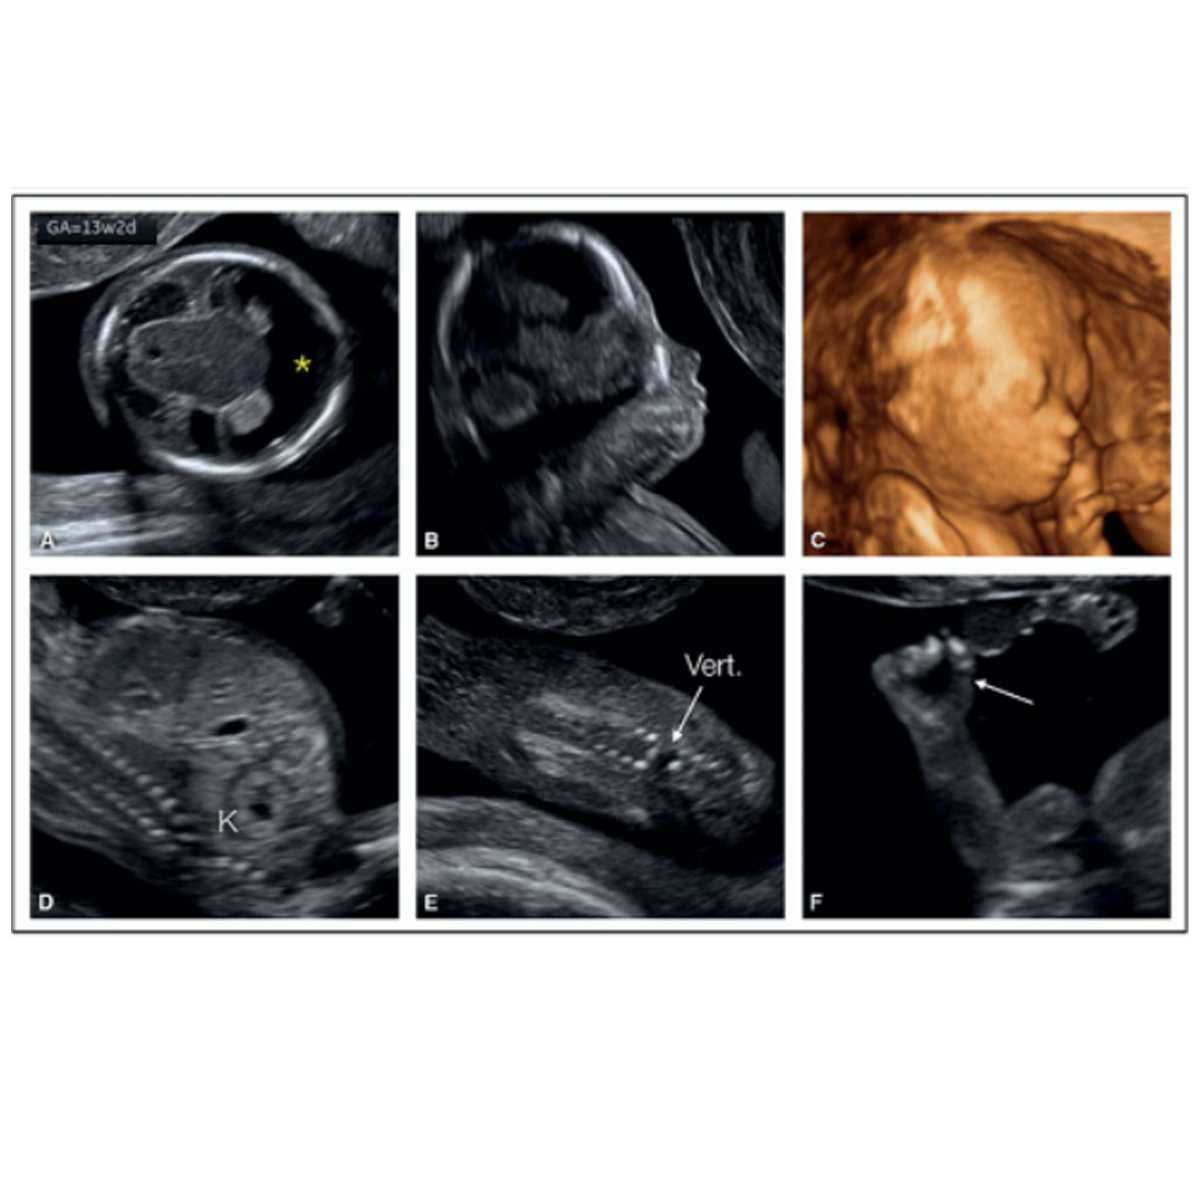

II. First Trimester Screening for Aneuploidies / Anomalies / Pregnancy Complications (Done between 11- 13+6 weeks / 45- 84mm CRL):

This is the most important scan in pregnancy, which provides information on preventable complications in pregnancy, like preterm delivery and hypertensive disorders in pregnancy. If picked up at right time, these problems can be prevented. Screening involves scan and a blood test – to measure hormones free b-HCG and PAPP-A. Also, more than 60%of major structural defects and 93% of chromosomal problems can be identified at this time. Babies with Down syndrome (Trisomy 21, most common chromosomal problem) have intellectual delay and first trimester screening is the most costeffective and efficient way of screening all pregnant ladies for Down syndrome.